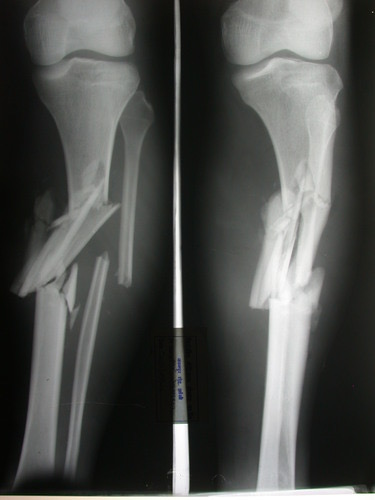

Communited fracture

Direct impact that shatters a bone into several fragments.